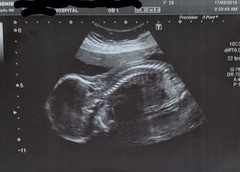

Hoping these are the correct edited ones!!

We nearly missed our anatomy scan completely thanks to the buses that either never turned up or got delayed/took ages to get to the hospital as it was packed. Thankfully someone had cancelled theirs just after when ours would have been so they very kindly squeezed us in. Would've completely understood if they couldn't have done it. All is looking okay. Placenta is definitely at the front but I think we're slowly getting there with feeling movements, and he still appears to be a boy 💙😊 I'm so, so relieved.

Congratulations @UnicornsandRainbows1 I'm glad you got to have your scan and that everything looks great! Your baby looks lovely. The pictures reminded me of my can of my DD. I just thought it was so amazing to see her perfect little spine. So intricate and perfect :) am I weird?! Lol xxxxxx

@54ChikiTIKI Not weird at all! 😊 It's so odd. I don't remember my DD's scan being so clear, but it's so odd how formed it is. I know it's 20 weeks but it's just insane!

@UnicornsandRainbows1 what a stunning and clear scan picture - congratulations x

Fantastic news on your scan @UnicornsandRainbows1 - that's an amazing pic of your son's spine! Ii'm so glad things are going okay for you.